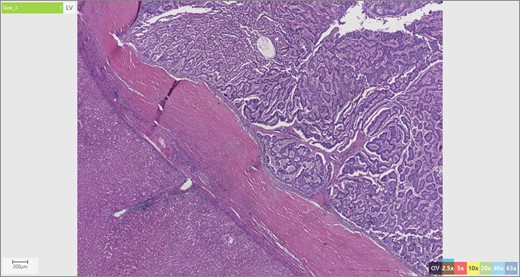

The patient’s surgical pathology was consistent with a low-grade neuroendocrine neoplasm arising within a mature cystic teratoma. The neoplasm took up 25% of the tumor volume and the rest was occupied by elements of a mature cystic teratoma. Histologically, squamous epithelium, sebaceous glands, thyroid, salivary gland, urothelium and gastrointestinal epithelium were all demonstrated (Figs 2–4). Final immunohistochemical analysis showed that the neuroendocrine neoplasm was reactive for: synaptophysin, AE1/AE3, STAT B2 and non-reactive for: CK 20, GATA3, CDX-2, CK 7, PAX 8, TTF 1, p 16, mammoglobolin, glypican 3, beta catenin, CD 117, DOG 1 and inhibin; thus, supporting its neuroendocrine origin from gastrointestinal tissue and consistent with a carcinoid tumor [12].

Skin adnexae and glandular elements of the mature cystic teratoma.